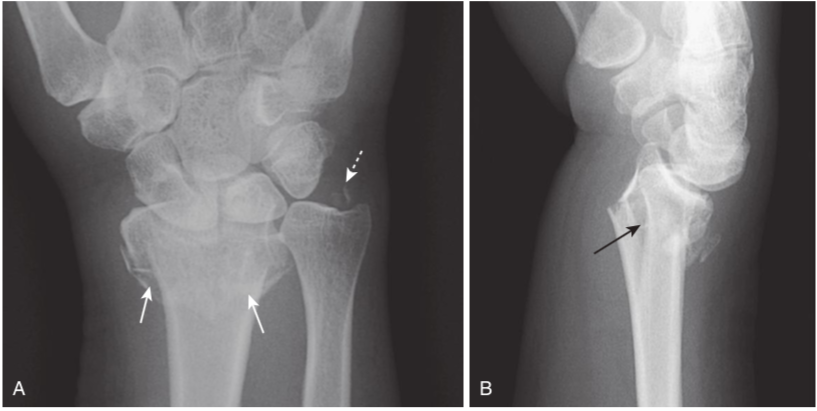

Greenstick and buckle (torus) fractures.

Incomplete fractures are those that involve only a portion of the cortex. They tend to occur in bones that are “softer” than normal, such as those in children (above) or in adults with bone-softening diseases such as Paget disease. A,There is a greenstick fracture, which involves only one part of (dotted white arrow)rather than the entire cortex (solid white arrow). B,This is a buckle fracture, in which there is buckling of the cortex (black arrows).